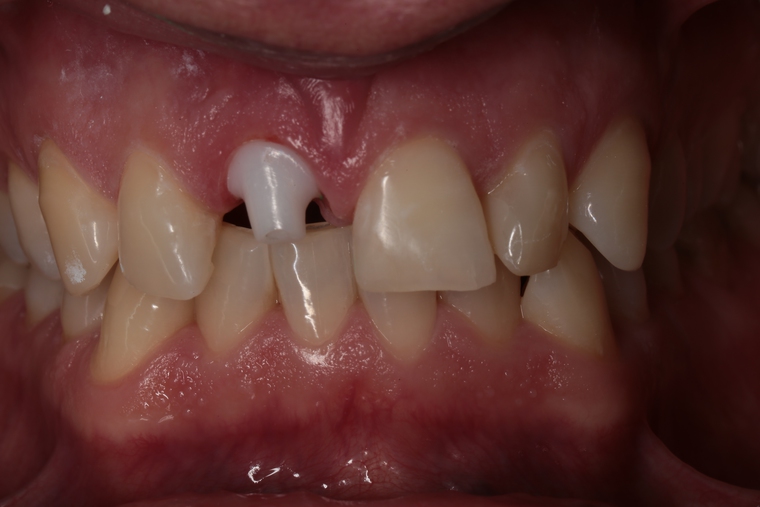

Ein Tätigkeitsschwerpunkt unserer Praxis in Salzburg ist die Implantologie. Wenn ein Zahn fehlt oder entfernt werden muss, sollte immer die Möglichkeit der Implantation im Vordergrund stehen. Ein Implantat verhält sich von den Eigenschaften genau so wie ein natürlicher Zahn. Egal ob nur ein einzelner Zahn vom Zahnarzt ersetzt werden muss oder ein ganzer Kiefer mit festsitzendem Zahnersatz versorgt werden soll, wir finden für Sie eine Möglichkeit, auch wenn die Voraussetzungen ausweglos erscheinen. Wenn möglich versorgen wir unsere Patienten mit Keramikimplantaten. Diese sind immun-neutral und können sehr oft direkt bei der Zahnextraktion eingesetzt werden. Für unsere Patienten ist daher meist nur ein operativer Eingriff notwendig!